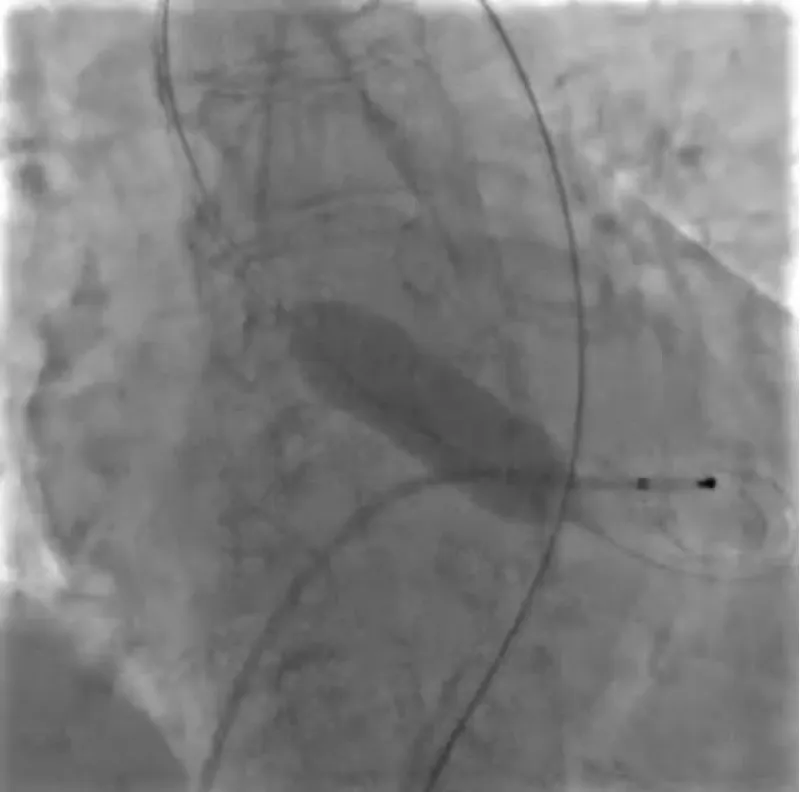

With the support of deep sedation, an angio-guided right femoral access was obtained, and a 12F introducer was advanced. We crossed the aortic valve with an Amplatzer left 1 catheter with a 0.035” wire and exchanged the wire with an extra-stiff Safari. We performed aortic Valvuloplasty with a Nucleus balloon 18 x 40 mm. (Figure 7) Then, we exchanged the wire and advanced an IMPELLA CP device, starting a protected PCI on LM. (Figure 8) An EBU 4.0 catheter was advanced, the stenosis was crossed on the Left Main (LM) and mid-Left Anterior Descending artery (LAD) using a BMW guide wire, and with the aid of a microcatheter a 0.014” Rotawire was positioned, followed by rotational atherectomy using a 1.5 mm burr on LM and mid LAD, (Figure 9) and a 2.0 mm burr on LM alone (Figure 10). This was followed by predilation with a 2.5 x 20 mm SC balloon and the implantation of a 2.5 x 32 mm Synergy drug-eluting stent (Figure 11). Then, the Left Main was predilated with a 3.5 x 12 mm NC balloon, and a 4.0 x 15 mm Xience Sierra drug-eluting stent was implanted and post-dilated with a 4.5 x 8 mm SC balloon (Figure 12). Immediate angiographic control confirmed a successful result. Then we removed the IMPELLA CP device and advanced a 14F e-sheath Edwards on the right femoral artery, crossed the aortic valve with a Safari extra-stiff wire, and performed a Sapien 3 23 mm valve implantation with a good angiographic result (Figure 13). Post-procedural echocardiographic and angiographic assessment confirmed the valve was correctly positioned, with no significant gradient and a minimal residual leak. The procedure was uneventful, and the patient was discharged on the fourth day with triple therapy: Aspirin 100 mg once daily, Clopidogrel 75 mg once daily, and Apixaban 2.5 mg twice daily. At the quarterly follow-up, the patient reported hospitalization for anemia, requiring a transfusion of 3 units of packed red blood cells. Endoscopic exams were negative, and hypochromic, normocytic anemia persisted. Given the patient’s CHA2D2-VASc score of 5, HAS-BLED score of 4, and recent dual Drug-Eluting Stent (DES) implantation, she was admitted for left atrial appendage percutaneous closure. Before this procedure, a repeat coronary angiography showed good results in the previously implanted stents (Figure 14). Subsequently, through a right femoral percutaneous approach using a 12F introducer, a 22 mm Amulet device was positioned for left atrial appendage closure (Figure 15). The procedure was completed without complications. At the 4-year follow-up, the patient presented in good hemodynamic status, with an echocardiographic ejection fraction of 55%. She continued on clopidogrel 75 mg once daily therapy.

Figure 7: Valvuloplasty with balloon Nucleus 18 mm.